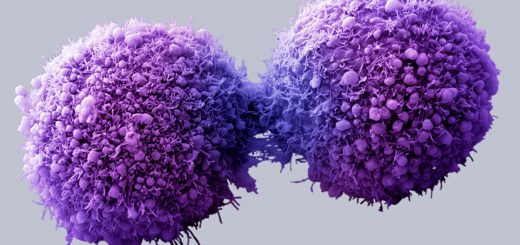

این افزودنی ها یا امولسیفایرهای موجود در غذا می توانند با تغییر باکتری های روده التهاب را بالا برده و شرایط را برای رشد سلول های مبتلا به سرطان کلون یا روده بزرگ فراهم کنند. خوب است بدانیم که سرطان روده بزرگ چهارمین دلیل مرگ و میر ناشی از سرطان در سراسر جهان است به طوری که در سال ۲۰۱۲ این بیماری منجر به مرگ ۷۰۰ هزار نفر شد.

برخی از رایج ترین امولسیفایرهای موجود در غذاهای فراوری شده عبارت هستند از پلی سوربات ۸۰ و کربوکسی متیل سلولز. خوردن غذاهایی که شامل این افزودنی ها باشند می تواند شرایط ملتهبی را درون دل و روده در طول زمان ایجاد کنند. همین امر می تواند احتمال ابتلا به سرطان رکتوم و روده بزرگ و همچنین بیماری التهاب روده را افزایش دهد که کولیت زخمی و بیماری کلون دو شکل رایج مورد آخر هستند.